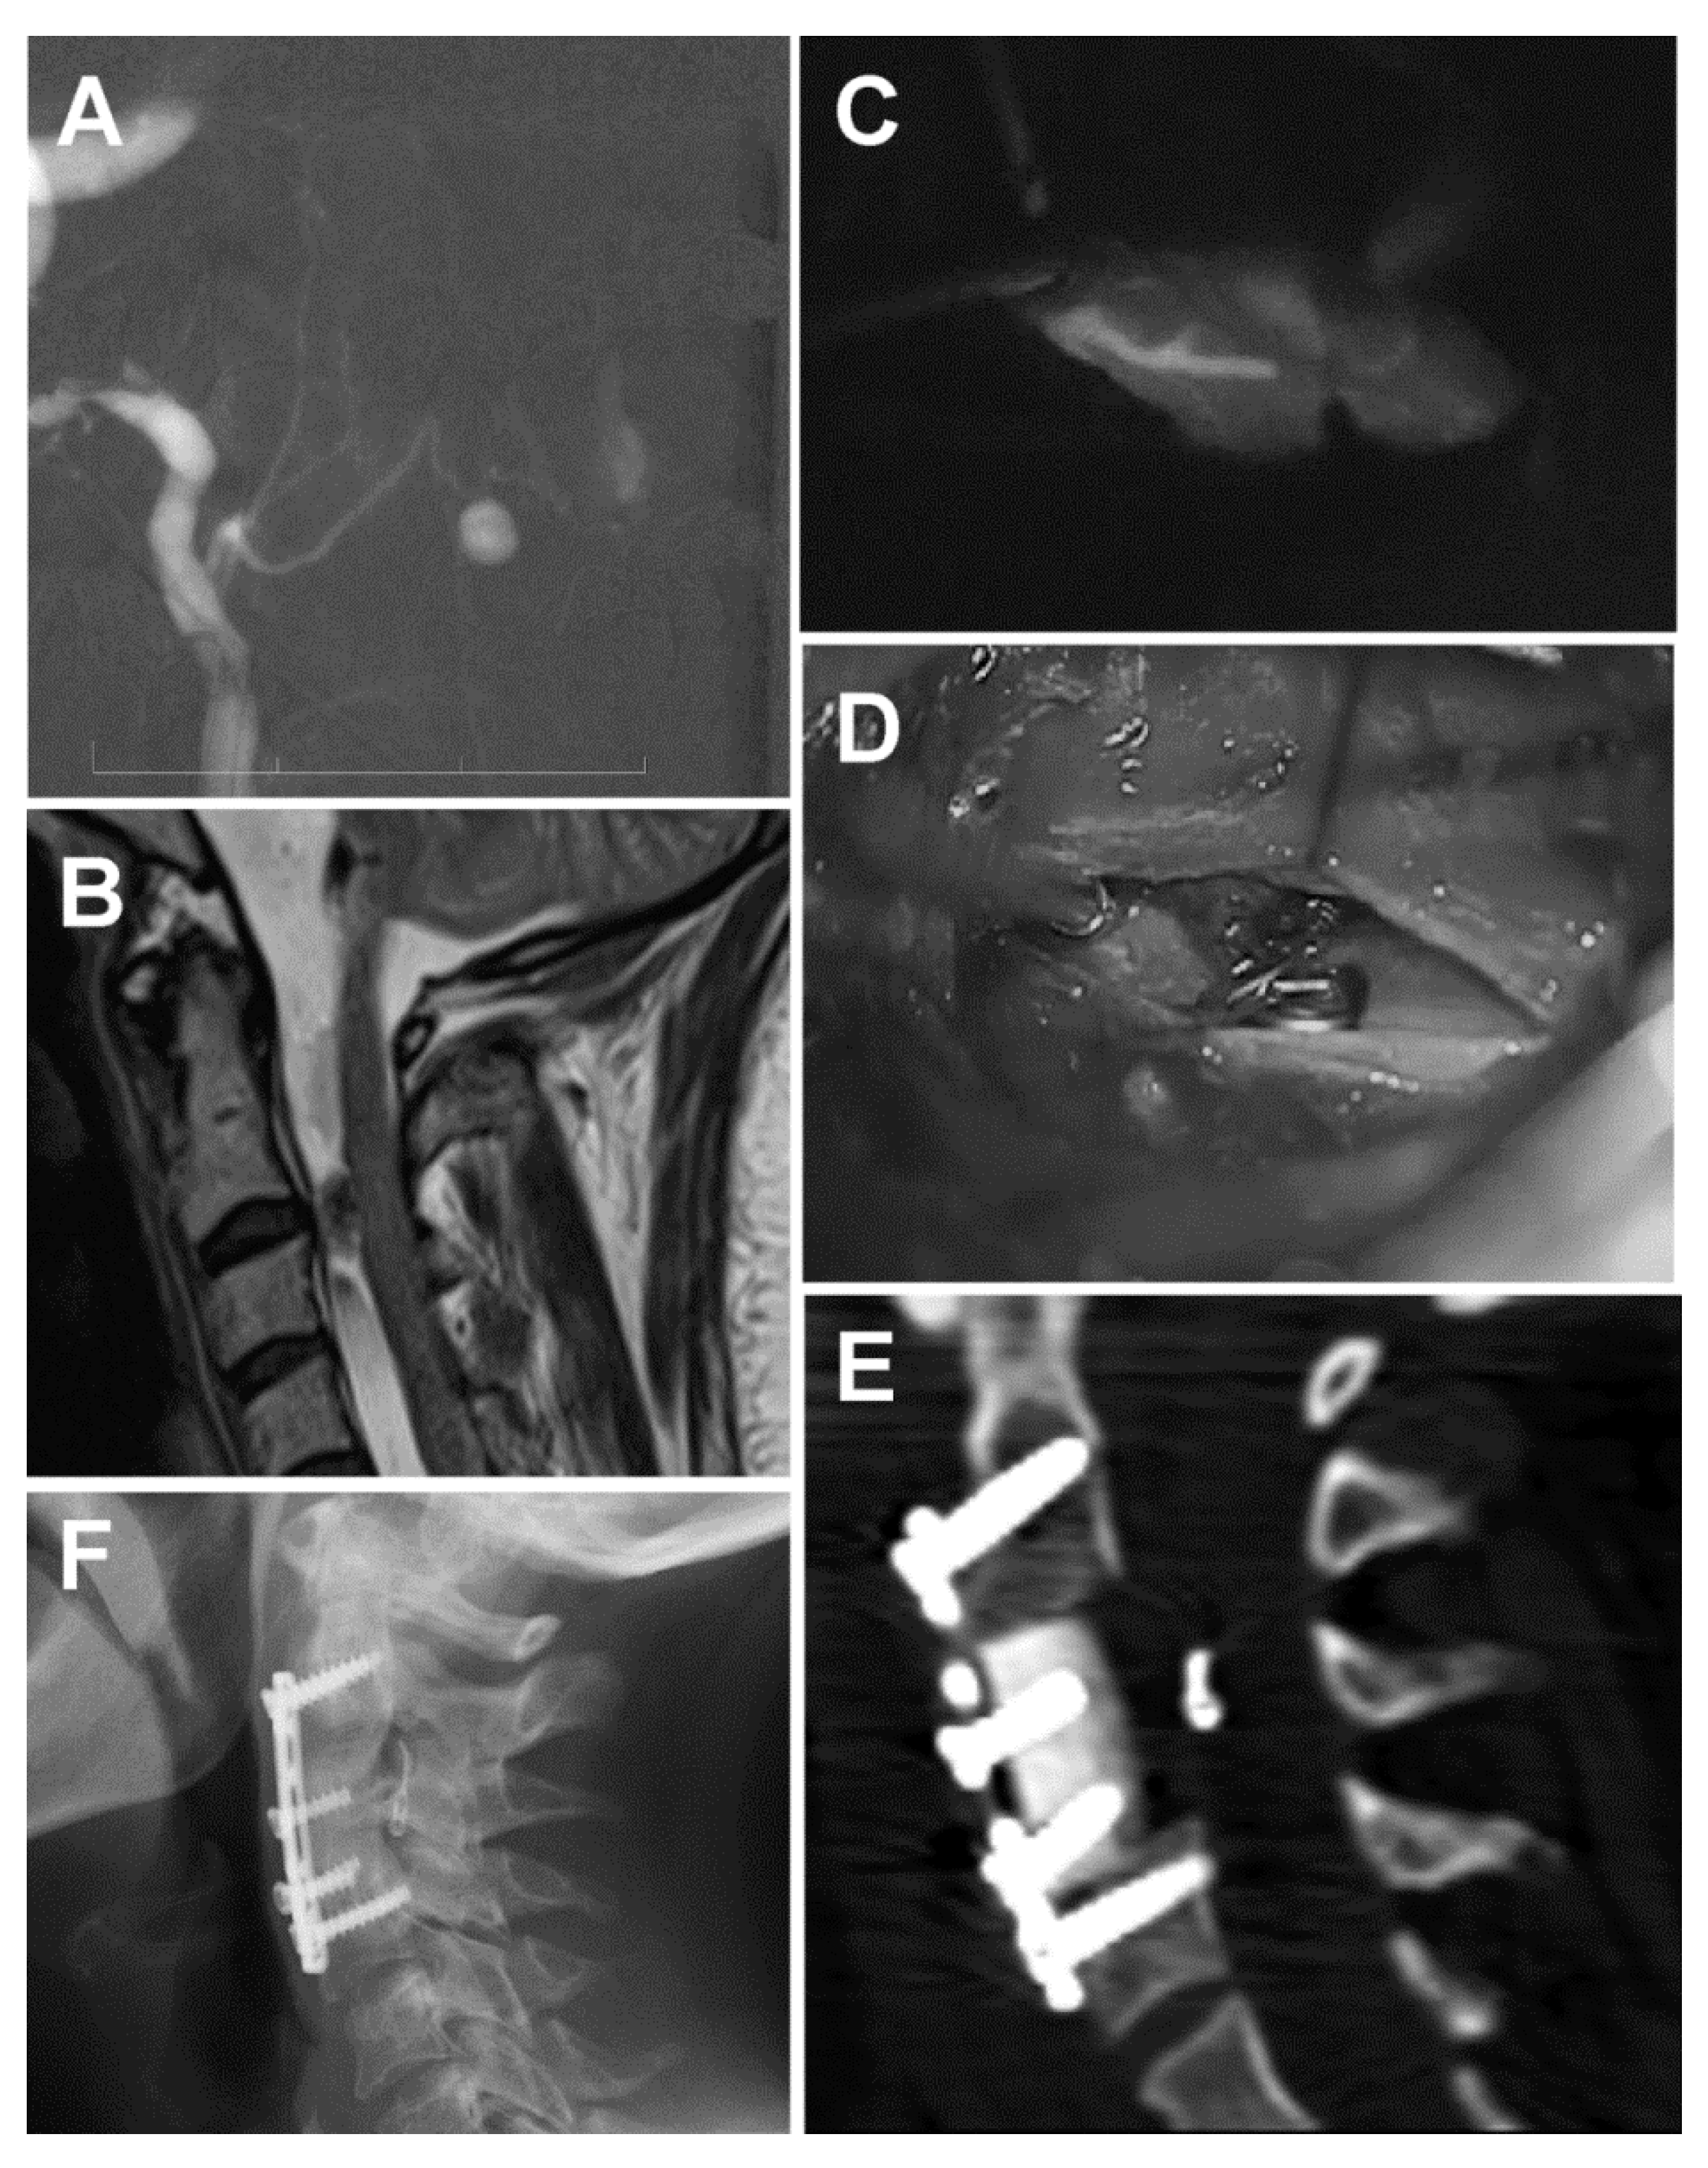

Spontaneous Subarachnoid Hemorrhage in a Patient with a Co-Existent Posterior Communicating Artery Aneurysm and Cervical Spine Aneurysm Associated with Ventral Arterio-Venous Fistula

Hejčl, A.; Lodin, J.; Cihlář, F.; Sameš, M. Spontaneous Subarachnoid Hemorrhage in a Patient with a Co-Existent Posterior Communicating Artery Aneurysm and Cervical Spine Aneurysm Associated with Ventral Arterio-Venous Fistula. Brain Sci. 2020, 10, 70. https://doi.org/10.3390/brainsci10020070